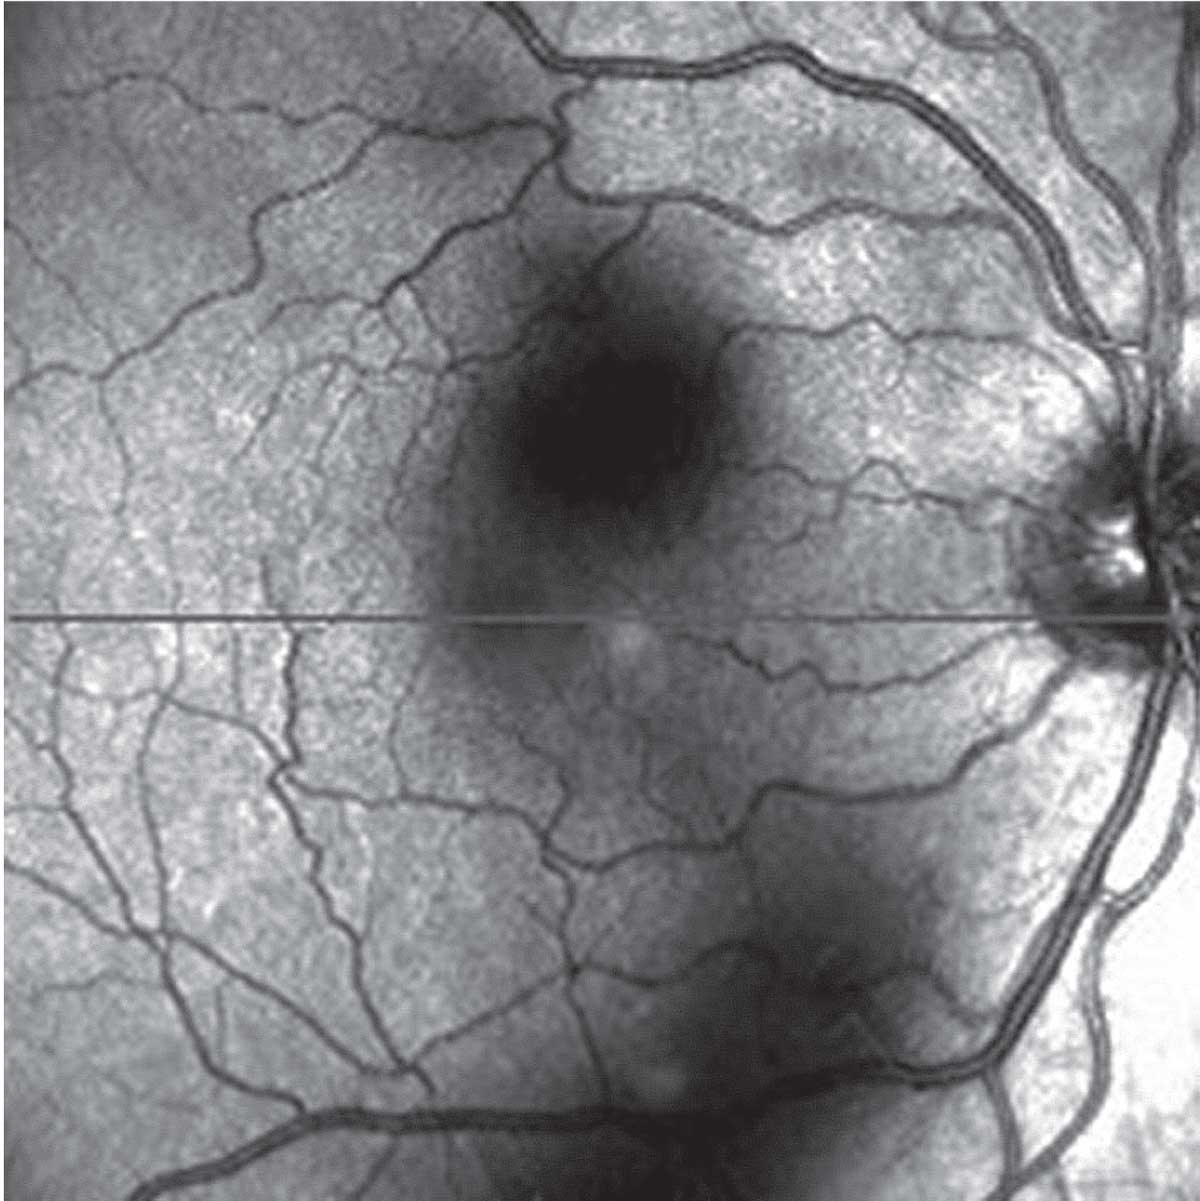

| Scanning laser ophthalmoscopy demonstrates vision-disturbing vitreous opacities. (Source: Huang L, et al. Vitreous floaters and vision: Current concepts and management paradigms. In Sebag J, ed. Vitreous – in Health & Disease. New York, NY; Springer; 2014:771-788. Used with permission) |

The first test is scanning laser ophthalmoscopy imaging on optical coherence tomography to assess the shadowing of the vitreous (Figure). On the main OCT image, the hyaloid face separation from (or adherence to) the retina can be visualized.